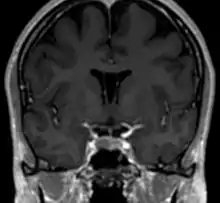

Полость прозрачной перегородки (лат. cavum septi pellucidi) — полость, находящаяся между листками прозрачной перегородки. Полость содержит ликвор, попадающий туда через поры в листках.[1]

Спереди полость ограничена коленом мозолистого тела; сверху — стволом мозолистого тела; сзади — передними ножками и столбами свода мозга; снизу — передней комиссурой и клювом мозолистого тела; латерально — листками прозрачной перегородки.[2]

Собственно полость прозрачной перегородки расположена на уровне основания передних рогов боковых желудочков мозга, а её распространение в заднем направлении в область тел боковых желудочков выделяют под названием полость Верге (лат. cavum vergae). Во время эмбрионального развития происходит закрытие полостей в задне-переднем направлении, из-за чего персистирование полости Верге при закрытой полости прозрачной перегородки встречается значительно реже.